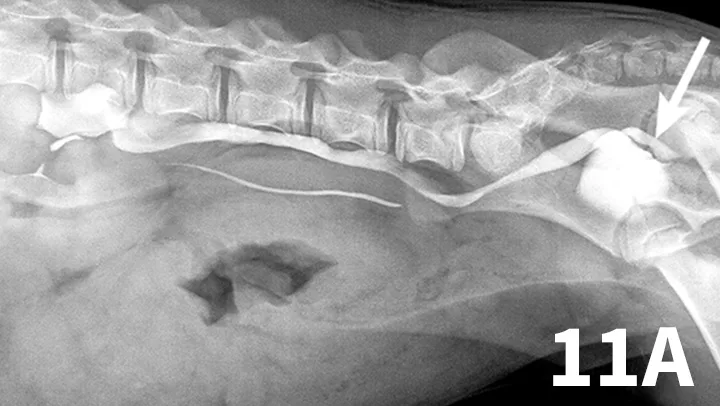

Figure 1.

An enlarged left kidney with an irregular shape (arrows) is noted on the VD view of a dog with renal adenocarcinoma. The left kidney measured 4.5 times the length of L2; normal kidney length in the dog is 2.5 to 3.5 times the length of L2.